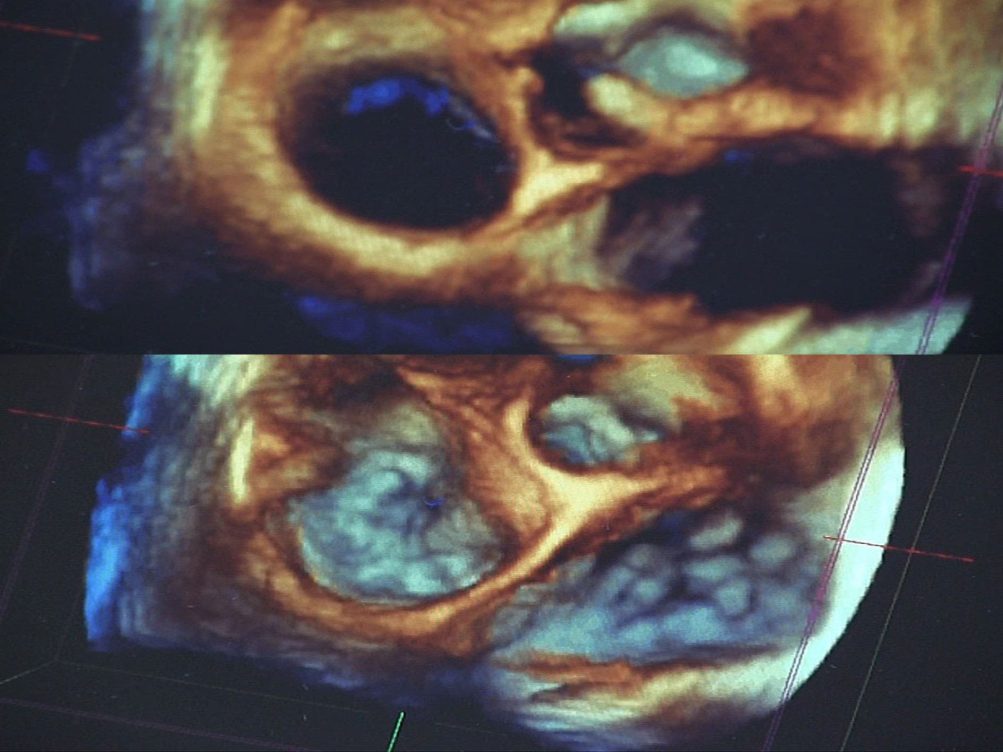

Ecocardiograma, tu corazón tridimensional